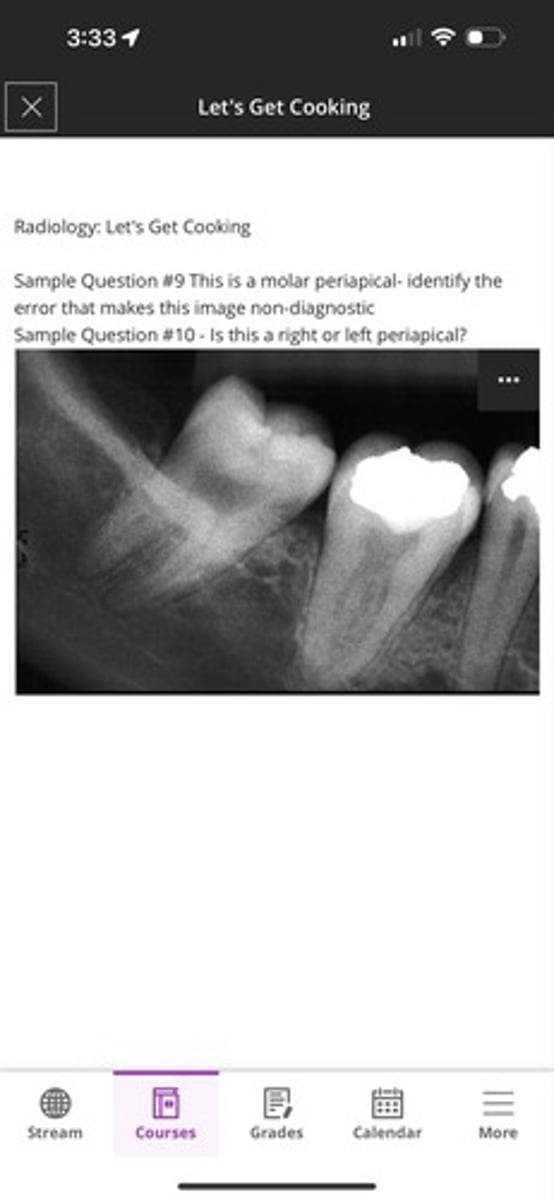

1. This is a molar periapical- identify the error that makes this image non-diagnostic

2. Is this a right or left periapical?

1. You cannot see the 2-3mm apical of both molars

2. right